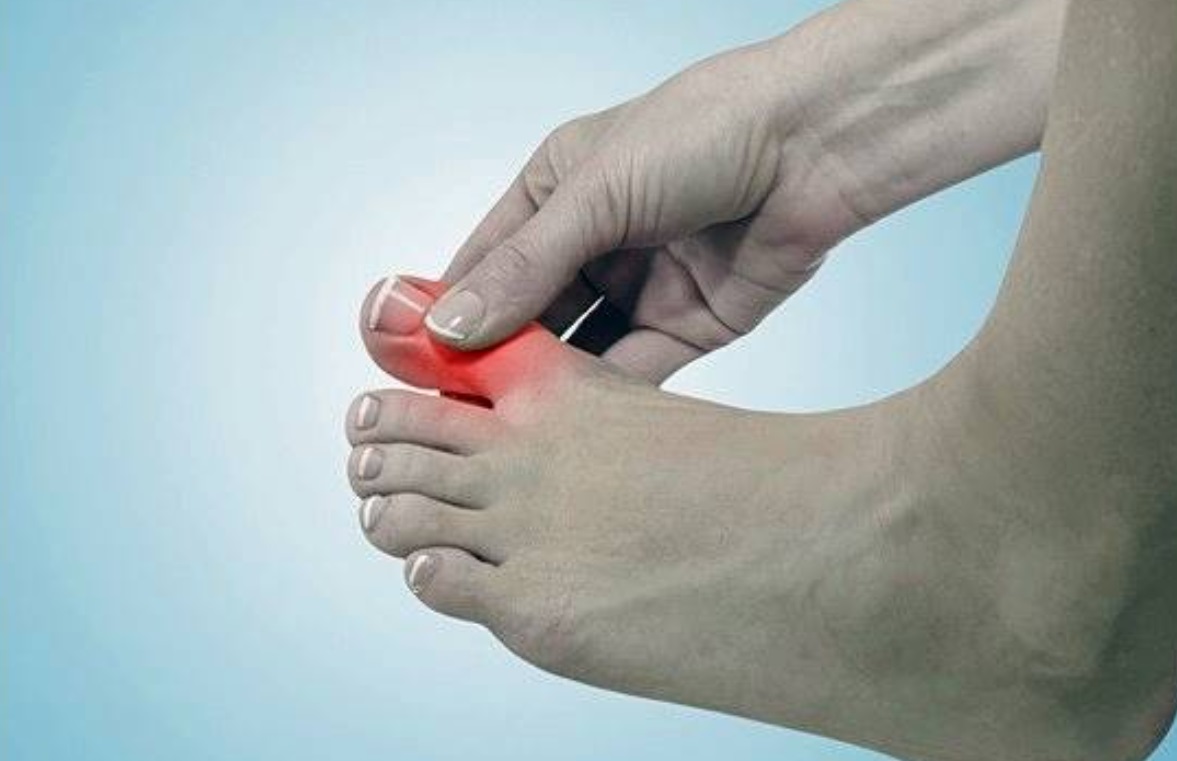

급성 통풍 발작은 갑작스럽게 발생하며, 대개 하루 이내에 최대 발생점에 도달합니다. 발작이 발생하면 통증이 극심하게 시작되고, 발적 부위는 붉고 따끔거리며 따끔거리고, 적출물로 인해 부어오릴 수 있습니다.

발적

발적 부위는 붉고 따끔거리며, 적출물로 인해 부어오를 수 있습니다. 이러한 발적은 대개 발작이 발생하는 부위에 나타나며, 발적이 심한 경우 걷는 것이 어려울 수 있습니다.